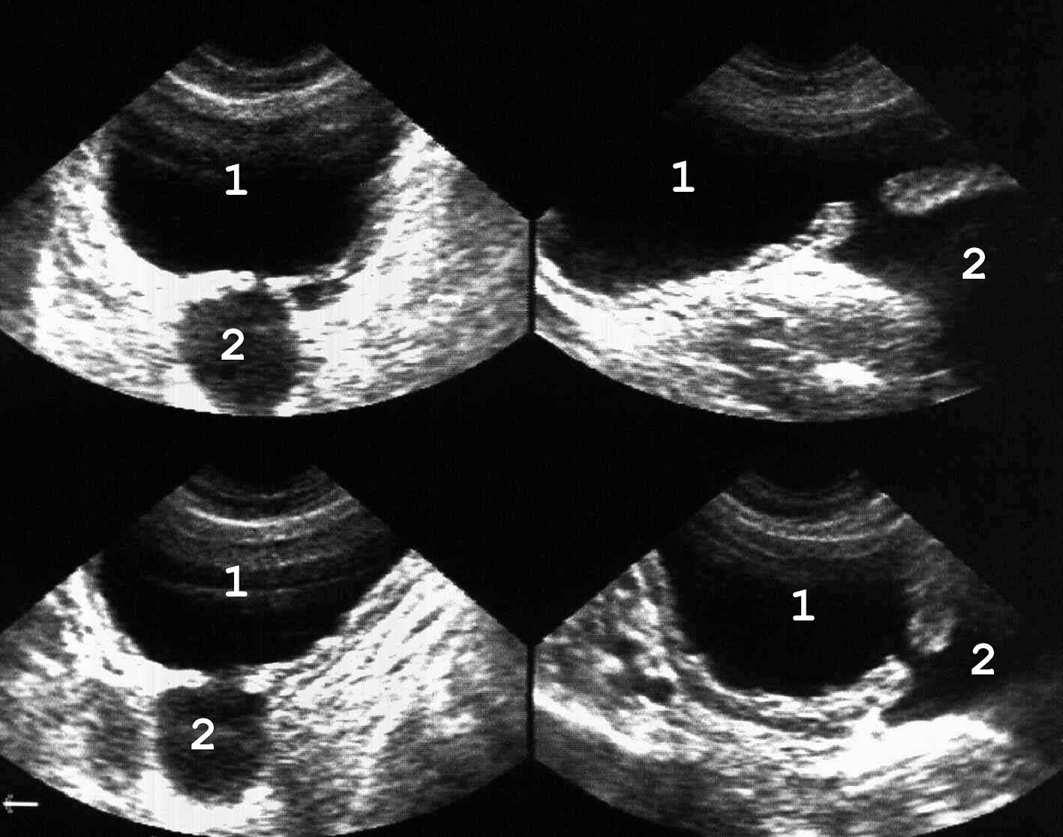

Представляет собой мешковидное выпячивание всех слоев стенки мочевого пузыря вследствие ее непра-вильного формирования (рис. 12). Дивертикулы могут быть одиночными и множественными, чаще располагаются на стенках латеральнее области треугольника, реже − на верхушке или у дна.

Дивертикул сообщается с полостью пузыря узким каналом и нередко имеет большие размеры, иногда превосходящие объем мочевого пузыря. Застой мочи в дивертикуле может приводить к камнеобразованию и возникновению там опухоли.

Рис. 12. Множественные дивертикулы мочевого пузыря: 1 − мочевой пузырь; 2 − дивертикулы. (Полипозиционное ска¬ни-рование, секторный датчик 5 МГц, “Siemens SL-1”).

Рис. 13. Киста яичника, по размерам сравнимая с мочевым пузырем и симулирующая дивертикул: 1 − мочевой пузырь; 2 − киста. Для дифференциальной диагностики необходимо повторное ультразвуковое исследование после микции. Объем кисты после этого остается прежним, а размеры диверти-кула изменяются. (Продольное сканирование, конвекс¬ный дат-чик 5 МГц, “Logiq-500”).